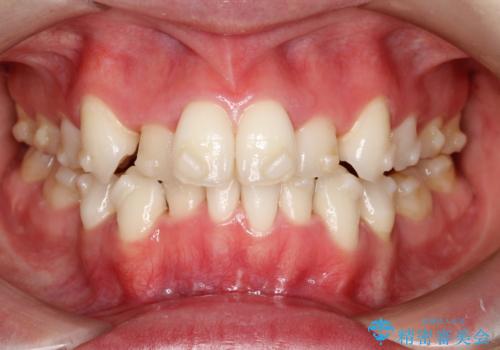

【抜歯インビザ】前歯の凸凹をなおしたい

- 前歯の凸凹を主訴に来院されました。

前歯はあまり下げる必要がなかったため、上下左右の第二小臼歯抜歯を行う治療計画としました。

途中、臼歯の近心傾斜を認めましたが、追加アライナーを使用することでリカバリーを行いながらインビザラインのみで治療を完了することができました。